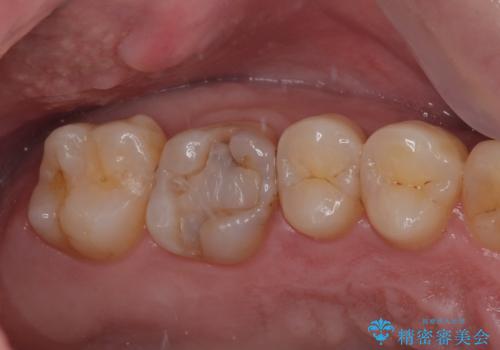

- 舌で触ると段差が気になるとのことで来院された患者様です。歯質がわずかに欠けており金属の詰め物の間に小さなギャップが生じていました。

咬み合わせも強い方なので物性、適合性に優れたゴールドインレーにて治療をしていくことになりました。

拡大鏡視野下で金属の詰め物、虫歯を除去し、ゴールドインレーに適した形に整えました。